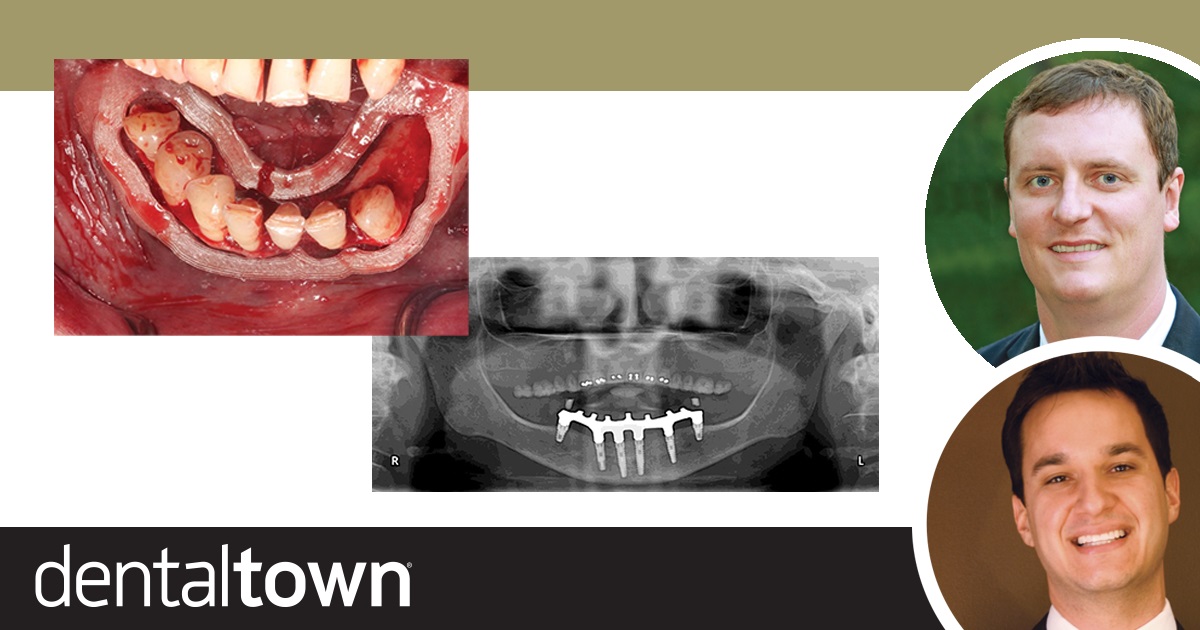

A failed implant nearly derailed this full-arch case from Drs. Danny Domingue and Cory Glenn—until a digital workflow and pterygoid rescue saved the smile and exceeded patient expectations

Drs. Cory Glenn and Danny Domingue discuss the digital advantage in full-arch implant dentistry and walk readers through an immediate-load FP1 implant restoration case.

Drs. Cory Glenn and Danny Domingue discuss a full-arch implant case that used a surgical guide 3D printed in the dental practice, and compare the case’s accuracy to a similar one performed without such a guide.